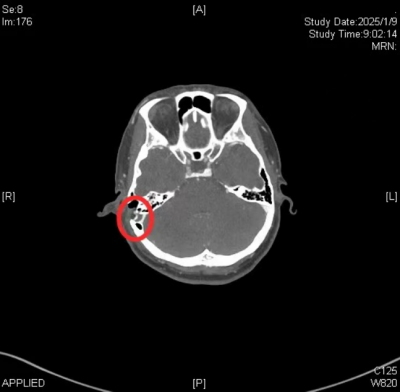

在冯永教授的带领下,耳科团队凭借丰富的经验和精湛的技术,结合术前影像资料,术中准确定位憩室位置,通过切除相邻乳突气房,充分暴露憩室内乙状窦,并通过自体筋膜成功回纳憩室,最后修复缺损骨壁,成功为张莲花实施了乙状窦还纳手术。术后,张莲花恢复良好,术后影像学检查评估,右侧乙状窦憩室部分已完全回纳,搏动性耳鸣症状完全消失,生活质量得到了显著提高。她感慨地说:“现在我终于能安心入睡了,感谢医生们让我重获宁静。”

术后CT提示(标注部位):右侧乙状窦成功回纳,与右侧乳突分离良好